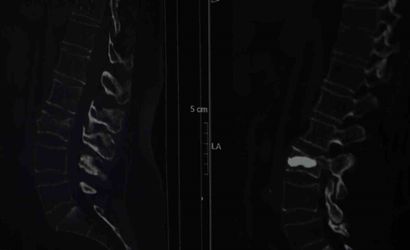

Ağrılar geçmeyince Şişli Hamidiye Etfal Eğitim ve Araştırma Hastanesi'ne başvurdu. Beyin ve Sinir Cerrahisi Uzmanı Doç. Dr. Şevket Evran ve ekibinin incelemelerinde, düşmeye bağlı olarak kemik erimesine bağlı bir omurga kırığı tespit edildi. Hastaya minimal invaziv yöntemlerle uygulanan kifoplasti 25 Ağustos günü gerçekleştirildi ve operasyon başarılı oldu.

Doç. Dr. Evran tedavi yaklaşımını şöyle anlattı: "Bu hastalarda travma sonrası kemik yoğunlukları düşük olduğu için omurgalarında kırık oluşma ihtimali normal popülasyona göre çok daha fazla görülüyor. ... Hastalar bu tarz travmalardan sonra ağrılarını birçok şeye yorabiliyor. Özellikle bel fıtığı, belinde kas güçsüzlüğü, düzleşme gibi hastamız da önce bel fıtığından şüphelenerek ağrılarının ona bağlı olduğunu düşünmüş fakat dirençli bir ağrı. Hiçbir medikal tedavi, ilaçla ağrıları dinmeyince durumun daha farklı boyutta olduğunu düşününce hastanemize başvurmuş."